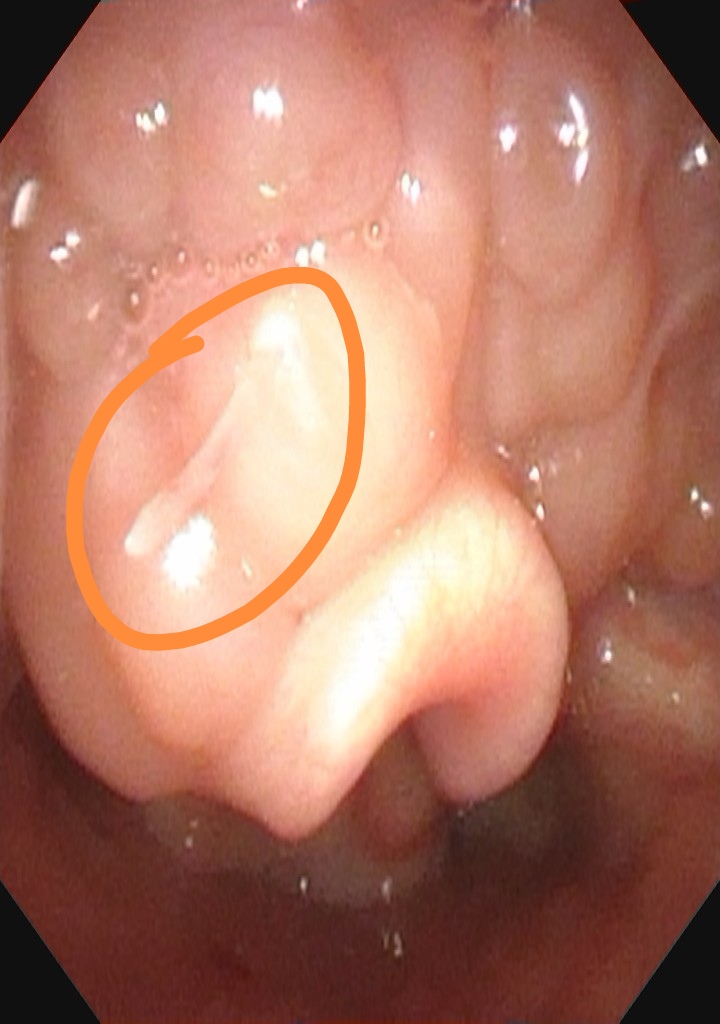

值班医生接诊后为琪琪进行电子鼻咽喉镜检查,结果显示舌根部偏左可见一鱼刺。医师在无麻下尝试用鱼骨钳取鱼刺,由于患儿咽反射敏感,配合度差,为防止二次损伤,于是在急诊全麻下为琪琪实施了咽内异物取出术,术中取出一约0.7cm长鱼刺。